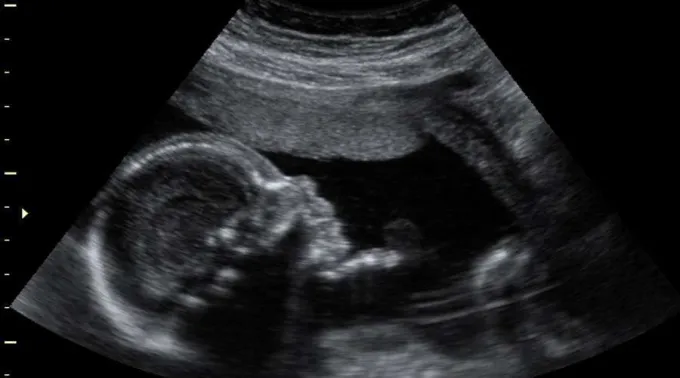

De acordo com a Lei de escolha da interrupção da gravidez, de 1996, o aborto é legal na África do Sul até a 12ª semana de gestação. Nos casos de estupro, incesto e dificuldades financeiras, essa prática é legal até 20 semanas.